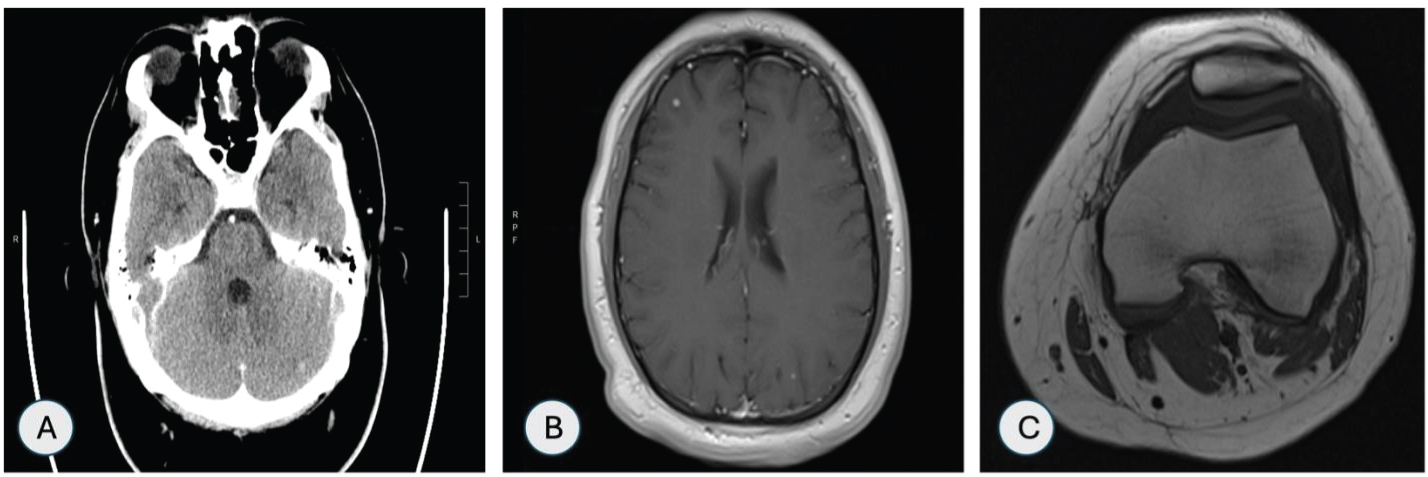

CT head was suggestive of small enhancing lesions in the right frontal cerebral lobe and left cerebellar hemisphere (Figure 5A). Magnetic resonance imaging (MRI) of head showed multiple small enhancing foci in bilateral cerebral and cerebellar hemispheres as shown in Figure 5B. MRI of left knee showed enhancement in the medial tibial epiphysis and metaphysis with adjacent soft tissue edema and large suprapatellar effusion (Figure 5C).

Figure 5: (A) CT head showing 5 mm enhancing lesion in left cerebeller hemisphere; (B) MRI head showing multiple enhancing foci in bilateral cerebral hemispheres; (C) MRI left knee showing large suprapateller effusion. View Figure 5